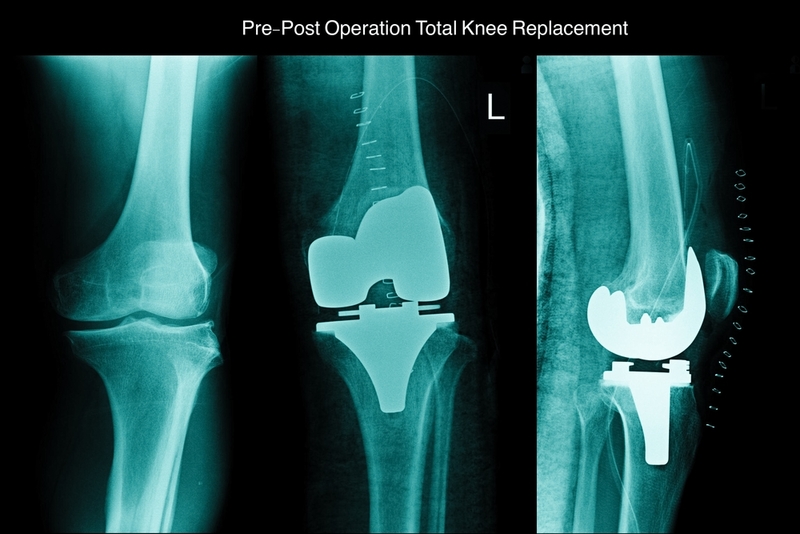

Total Knee Replacement (TKR) surgery is a procedure to replace the affected knee joint with artificial material and serves as a saviour for patients struggling with severely damaged knee joints. "Joseph Maina Githemba from Kenya, was advised replacement for his left knee owing to an accident he had met 15 years ago," a spokesperson of Max Hospital, Saket said.

Joseph was trained to do exercises that would be required after his recent surgery. "Dr Vikram and his team performed the first daycare TKR in north India using minimally invasive technique that included no tourniquet, injecting local anaesthesia into the skin before incision as well as into tissues at regular intervals, meticulous dissection, catching all bleeds before closure of the wound and injection of tranexamic acid to reduce bleeding post-operation," the hospital said in a statement.

Total knee replacement has been a time-taking procedure with around three hours of surgery and considerable hospital stay post operation, the doctor said. "Daycare TKR has served as a revolution in healthcare industry with minimal incision, exposure, blood loss and hospitalisation. It also brings down the total cost by 30-35 per cent compared to standard TKRs," Vikram claimed. "Choosing the right patient is crucial and no comorbidities in Joseph's case made this first daycare TKR procedure a success," he said.